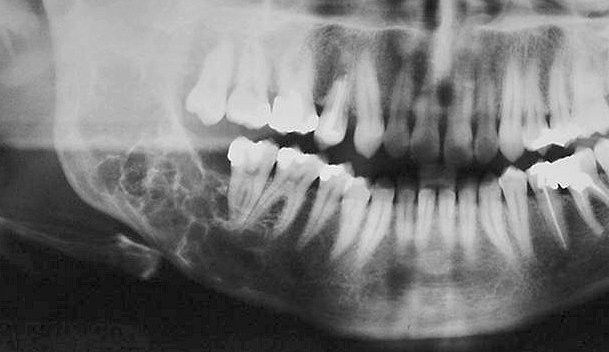

- Radiographically is typically multilocular. The internal septa are thin and straight forming a tennis racket or a honeycomb appearance.

- Usually has well defined borders.

- Adjacent teeth can be displaced but rarely resorbed.